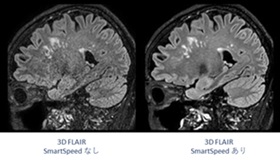

新しいMRI装置は、2025年5月から稼働を開始しました。- ポイント1:『短時間かつ高画質』